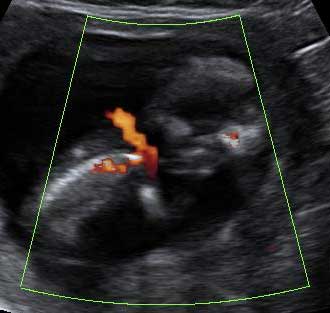

Las ecografías permiten distinguir el sexo del feto. En este ultrasonido en 3D, el bebé de 11 semanas de gestación se cree que es una niña, aunque no se puede asegurar todavía. Los genitales externos se empiezan a formar en la semana 8 de embarazo y terminan hacia la semana 12.

El tubérculo genital (flecha) apunta hacia abajo, lo que hace muy probable que se trate de una mujer.